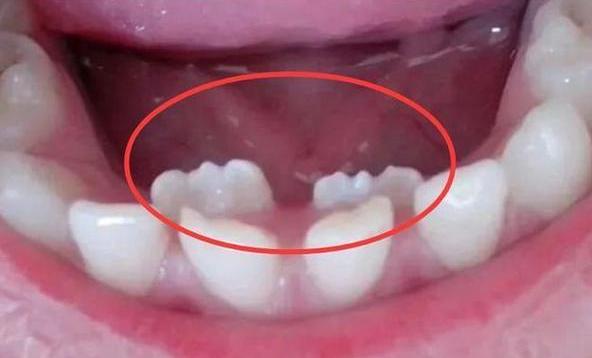

Q6.出现“双排牙”咋办?到底要不要拔?

“双排牙”又叫“乳牙滞留”,简单说就是新牙已经长出来了,旧牙还不肯掉。

曲面断层片怎么看换牙与身高有关吗?关于孩子换牙的所有疑问一篇说清_https://www.jmylbn.com_新闻资讯_第14张

关于双排牙到底要不要拔,是一个有点争议的话题。

国内外学者有争议⚠️

国内教科书上建议尽早拔除滞留乳牙,尤其是上颌“双排牙”。

而国外学者Gellin等监测了44名儿童,发现95%的下颌恒中切牙在8岁2个月前都能自行调整到正确位置,下颌侧切牙至少在8岁4个月时能自行调正,考虑到双排牙可能会造成家长的焦虑情绪,他们认为7岁半前出现“双排牙”没必要拔除。其他考虑还包括第一次就诊时就拔牙可能会影响孩子和医生建立融洽关系等。

所以,双排牙要不要拔,并非简单的Yes or No,下面分享一下我在临床工作中的一些观点:

1. 首先,可以肯定的是,及时拔掉滞留乳牙有利于新牙往前排齐和牙齿的清洁,对孩子的口腔健康没有坏处。

2. 最终新牙能否完全排齐,主要看乳牙是否“有缝”。乳牙“有缝”是牙弓位置充足的重要标志之一。

对于下颌牙齿,只要牙弓位置充足,滞留的乳牙无论是晚一点自行脱落还是提前拔除,恒牙都能在之后的数月内往前排齐。而如果牙弓空间不够,即使提前拔除了滞留乳牙,恒牙最终仍可能无法完全排齐。

曲面断层片怎么看换牙与身高有关吗?关于孩子换牙的所有疑问一篇说清_https://www.jmylbn.com_新闻资讯_第15张

曲面断层片怎么看换牙与身高有关吗?关于孩子换牙的所有疑问一篇说清_https://www.jmylbn.com_新闻资讯_第16张

图注:左图:乳前牙有缝,右图:乳前牙没缝

3. 上颌“双排牙”应尽早拔除,避免造成“地包天”。